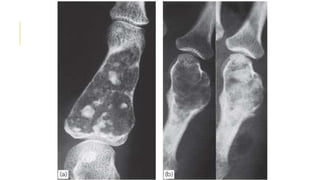

GIANT-CELL TUMOR

Giant-cell tumour is a lesion of uncertain origin that appears

after the end of bone growth.

Most commonly in the distal femur, proximal tibia, proximal

humerus and distal radius.

About one-third of these tumors remain truly benign; one-third

become locally invasive and one third metastasize.

Present as pain at the end of a long bone; sometimes there is

slight swelling.

Pathological fracture occurs in 10–15% of cases.

x-ray show a ‘cystic’ (i.e. radiolucent) area situated eccentrically

at the end of a long bone. Unlike any of the other ‘cystic’ lesions,

it always extends right up to the subchondral bone plate.